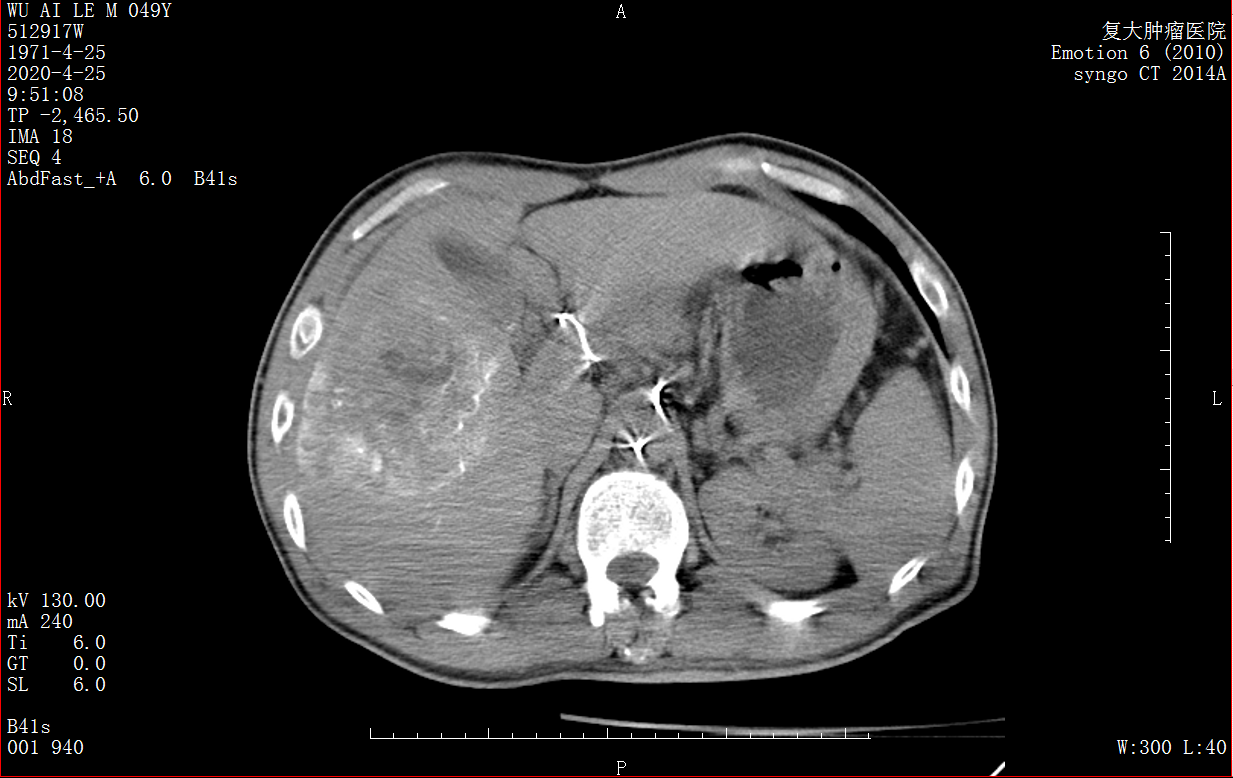

MDCT с контрастным веществом работает в операции для найти лучшее место эмболии

MDCT показала лучшее место эмболии, контрастное вещество только действует для опухолей.

Снимок MDCT после операции показал, что эмболирующий препарат находится в опухоли печени и все опухоли полностью вылечены, а нормальная ткань печени не эмболизирована, что указывает на отсутствие повреждения нормальной ткани печени.